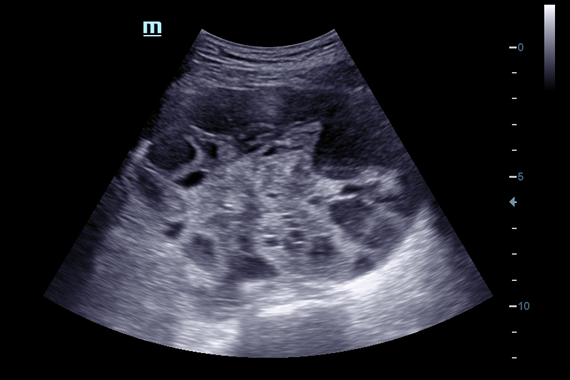

Система ультразвукового исследования Mindray DC-60 EXP X-INSIGHT является новейшей разработкой для проведения комплексных обследований на высшем уровне. Она обеспечивает решение самых сложных задач в таких областях, как кардиология, акушерство и гинекология, сосудистые заболевания, педиатрия и многие другие.

DC-60 EXP X-INSIGHT - это современный стационарный УЗИ-аппарат с функцией сенсорного управления и очищенной гармонической визуализацией, обеспечивающей лучшее контрастное разрешение и технологию 4D-визуализации. Он оснащен 21,5-дюймовым монитором, который может поворачиваться на 180 градусов, что удовлетворяет потребности врачей в качественной ультразвуковой диагностике.